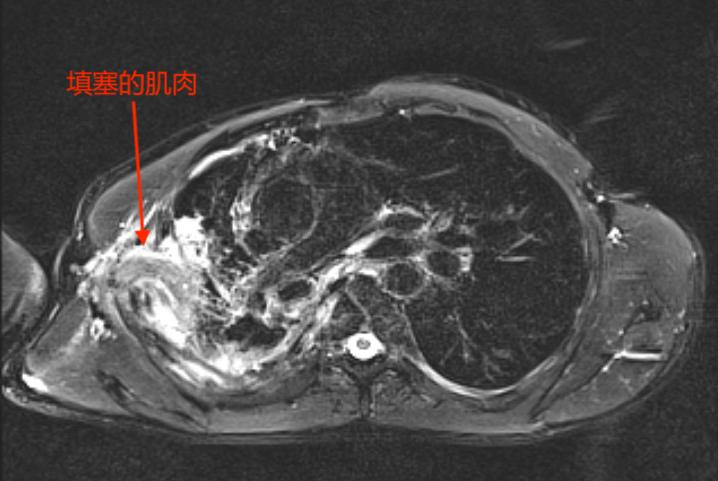

最终,专家们决定进行多学科联合手术。由呼吸科先进行支气管镜下瘘口封堵;然后,胸外科胸腔镜下清创;最后,由沈立锋副主任医师进行肌肉瓣覆盖瘘口、完全填塞胸腔彻底消灭脓腔。

起初,沈医师决定用体积大、血运又非常丰富的背阔肌来填塞胸腔。

然而,手术总是存在各种变化。沈医师发现,多年的肺部疾病使杜先生丧失了大部分劳动能力,肌肉严重萎缩,单独用这块肌肉填塞胸腔,远远不够。

医生的智慧显得尤为关键,经验丰富的他当机立断,马上调整手术方案,选择增加背阔肌和胸大肌两组肌瓣联合填塞关闭胸腔。

运用肌瓣、大网膜等自体组织对脓腔进行填塞,可彻底治愈脓胸。临床上最常用的为背阔肌、胸大肌、腹直肌瓣或肌皮瓣。肌皮瓣不仅有足够的体积和面积填补胸腔、修补皮肤溃疡,并且其丰富的血供可以有效地进行局部抗炎。带有丰富血运的肌肉组织覆盖内置封堵器并与周围组织愈合,亦可以辅助关闭瘘口,防止再发。所以肌皮瓣是消灭脓腔的最佳选择。肌皮瓣的选择要根据脓腔的大小、形状以及位置而定,常可多块联合应用治疗。